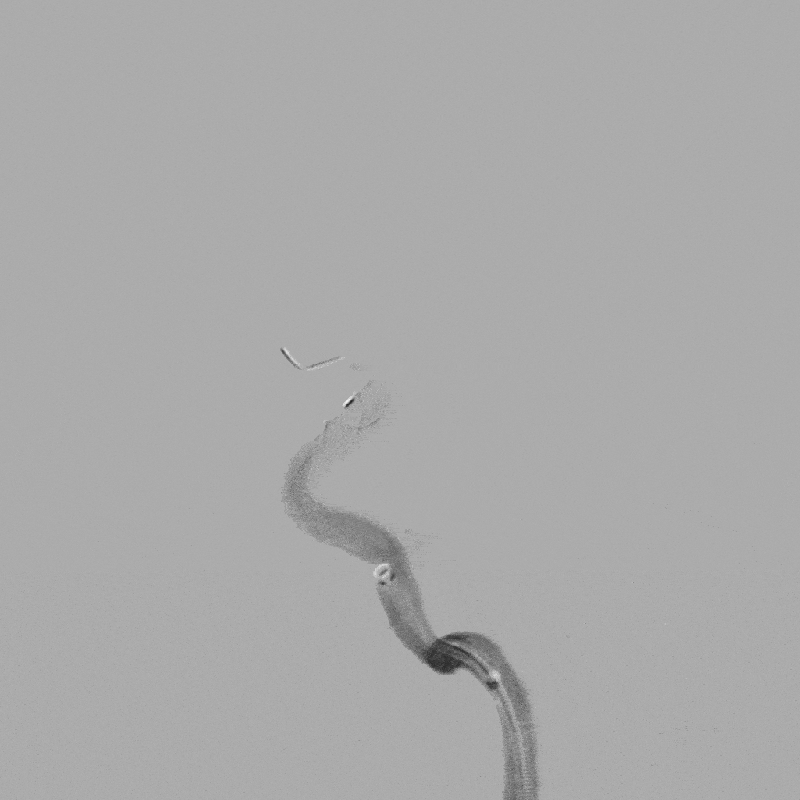

2022-2-21 右侧颈内动脉血流导向装置重建术(Tubridge)

8F Guiding+5F Navien+FasTrack

R-ICA血流导向装置(Tubridge3.5*20mm)

术后当日病情

术中10:00肝素化30mg。

10:30 手术结束。

10:50 麻醉清醒,返回病房,替罗非班1.0ml/h。

14:30 患者诉轻度头痛。

神清语利,肢体活动正常。

15:10 停用替罗非班,急查头颅CT。

少量出血(SAH?实质?),无神经功能受损。

停用波立维,继续吲哚布芬0.1g 2/日。